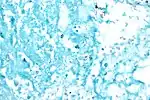

![]() M. tuberculosis (stained red) in sputum | |

Acid fast bacilli, Ziehl–Neelsen stain.